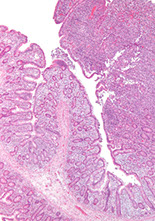

MC is alpha HCD - variant of extranodal marginal zone lymphoma of MALT;

occurs in young adults (10-30 yo) from Mediterranean and affects the GI tract, known as immunoproliferative small intestine disease (IPSID) thus causing sx of diarrhea, fever, abd pain, hypoCa+ and wasting

- may result from chronic infx c C. Jejuni

Genes: deletions in IGHA gene present that cause defective heavy chain protein that cannot bind light chain to make a complete immunoglobulin

- does not have t(11;18)

Px: may completely remit c abx; most progress to DLBCL; some anthracycline-chemo tx may help